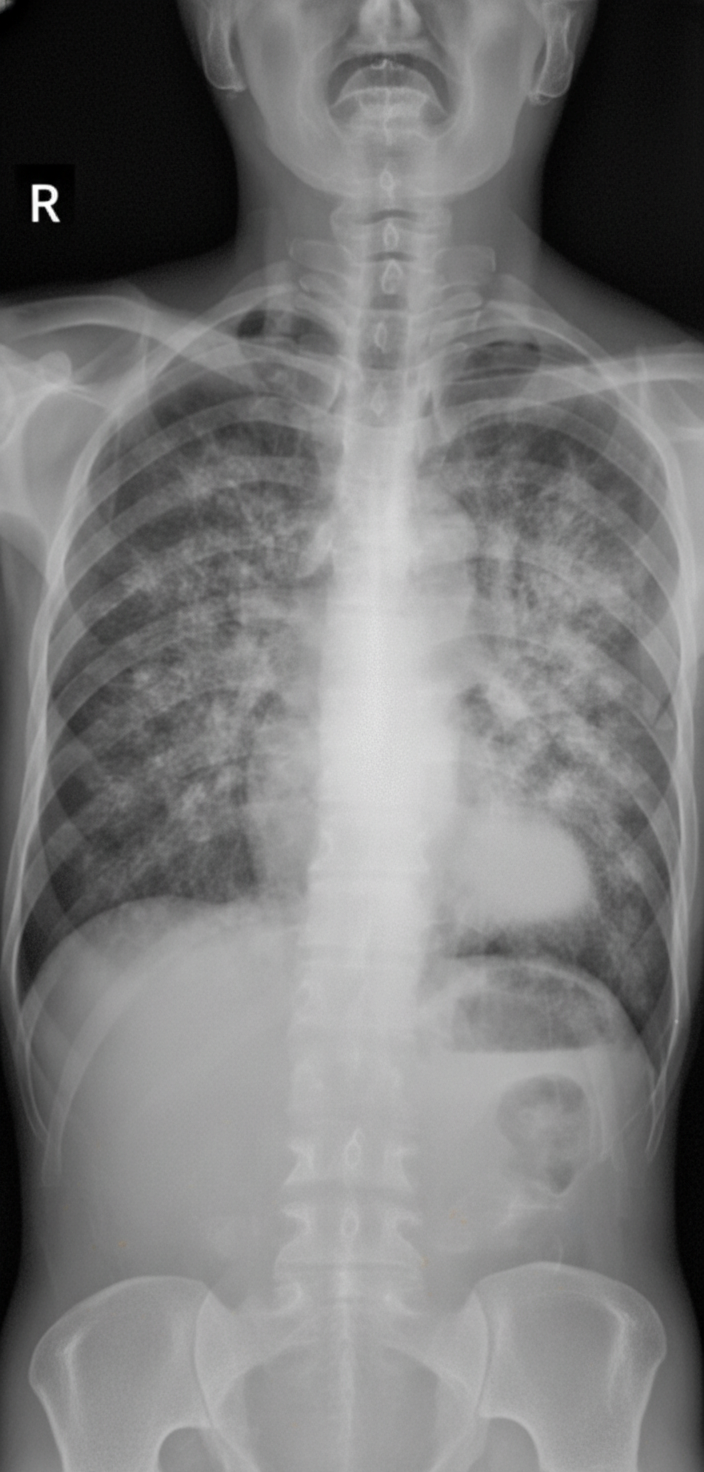

A 67-year-old female presents to the emergency room with dry cough and malaise. She has no other complaints. She has a past medical history of a meningioma status post resection complicated by hemiplegia and has been managed with dexamethasone for several months. Her vital signs are T 100.4 F (38 C), O2 93% on room air, RR 20, BP 115/75 mmHg. Physical examination is notable for crackles bilaterally. A chest radiograph is obtained (Image A). The patient is admitted and initially treated guideline-compliant antibiotics for community-acquired pneumonia. Unfortunately, her respiratory function deteriorates. An arterial blood gas is drawn. On room air at sea level, PaO2 is 71 mmHg and PaCO2 is 34 mmHg. Induced sputum samples reveal organisms on methenamine silver stain. What is the best treatment strategy for this patient?